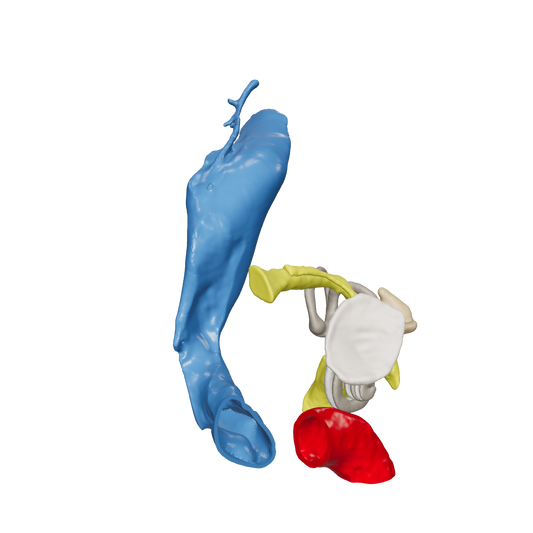

Dissect each one to learn human temporal bone anatomy, hearing and vestibular systems.

*High Contrast Colors* 3D Temporal Bones to Introduce Anatomy (6-pack)

Regular price $402.00 USDRegular priceUnit price per -